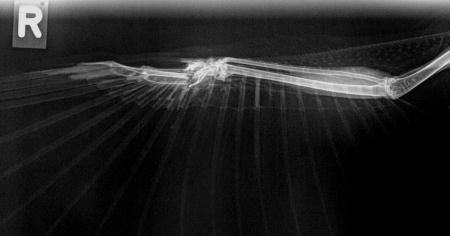

Trasportato subito allo studio veterinario Keller e Pedretti per un controllo, la triste scoperta: Vira era stato colpito da una scarica di pallini che gli avevano fratturato l’articolazione dell’ala destra. Il gufo ha dovuto essere soppresso sia per l’impossibilità di recuperare l’ala sia per lo stato di salute generale e la forte infezione già presente.